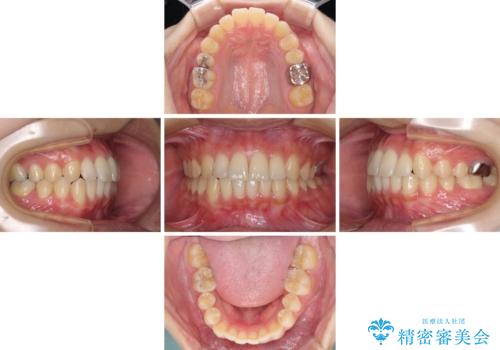

- 前歯のクロスバイトを気にして来院され患者様です。

治療期間が世界的な感染症の流行時期と重なったため、海外と日本での往来が困難となり、治療継続が懸念されました。

それでも、しっかりとマウスピースを装着してくださったので、大きなトラブルもなく治療を終えることができました。